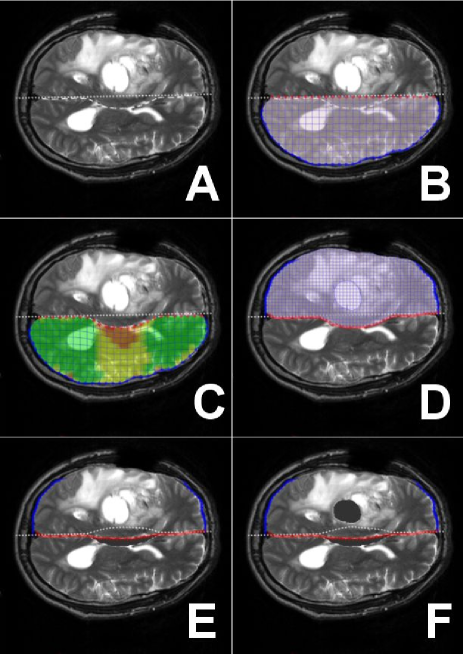

Figure 3 depicts a 2D simulation of the initial brain-shift at dura opening and subsequent brain sagging after cyst and tissue resection. In this case, intracranial pressure excess creates an initial bulging, although this behaviour is not systematically observed.

Figure 3-A: This preoperative T2 MRI scan shows the conflict between the two hemispheres. The dashed line shows the actual hemispheres interface while the dotted line indicates the initial interface position i.e. the middle of the skull.

Figure 3-B: Mesh of the contralateral hemisphere. The red nodes are ‘pilot’ and the border blue nodes are ‘sliding’.

Figure 3-C: Compression of the contralateral hemisphere. The color code displays the stress within the elements.

Figure 3-D: Mesh of the hemisphere with tumor.

Figure 3-E: Right after the dura opening, the stress computed in step C is applied to the upper mesh, which causes the brain to bulge.

Figure 3-F: Gravity, cyst drainage and tissue resection cause the brain to sag.